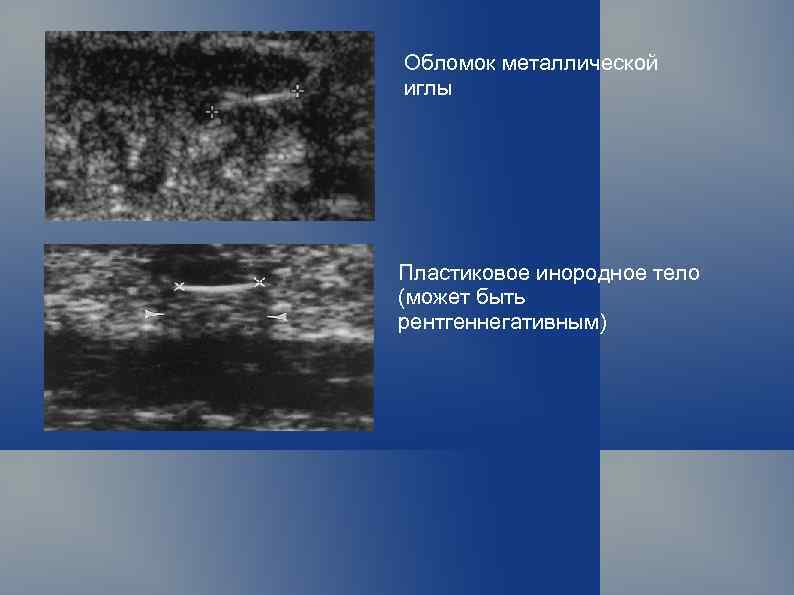

Обломок металлической иглы Пластиковое инородное тело (может быть рентгеннегативным)